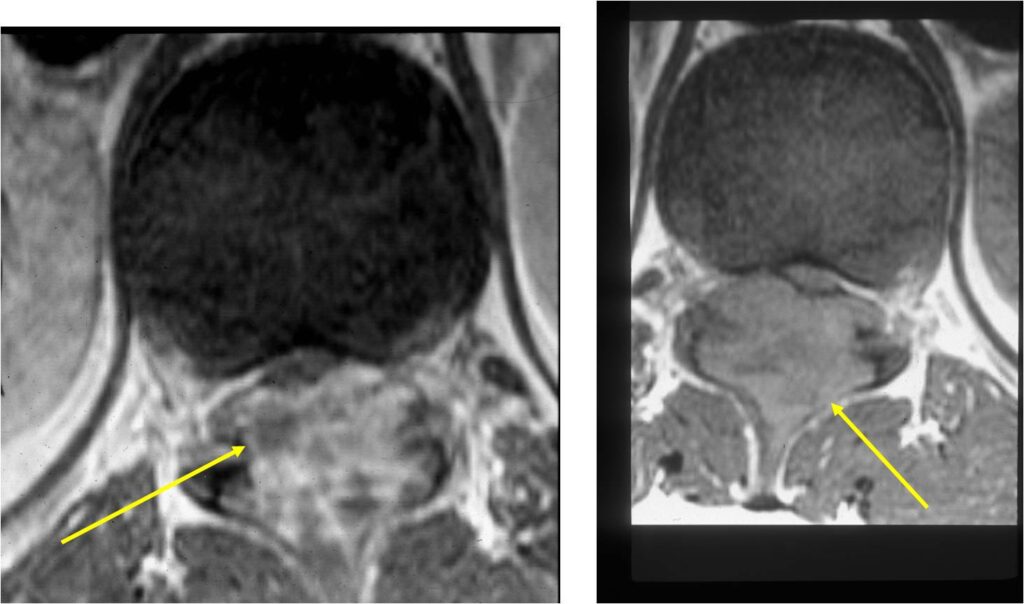

MRI:

- Also useful in determining extent

- There is often extensive edema around the tumor in the surrounding bone and soft tissues that can lead to a misdiagnosis of a malignant tumor.

- Spine (40% of cases; usually posterior elements)

- Spinal lesions may be accompanied by muscle spasms, scoliosis and neurological manifestations